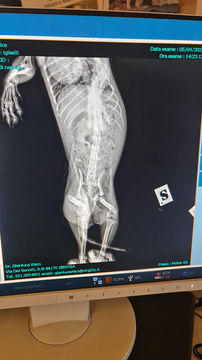

Pulce wurde vor einiger Zeit von einem Auto angefahren. Davon haben wir bereits berichtet. Jetzt war sie bei einem Orthopäden, der die kleine Maus untersucht und umfassend geröntgt hat. Und leider sieht es an der Hüfte für Pulce gar nicht gut aus. Durch den Unfall sind beide Femurköpfe aus der Hüfte herausgesprungen, es gibt natürlich bereits Verwachsungen und die ganze Hüfte ist schief. Die einzige Möglichkeit ist nun die Hüfte wieder zu richten, indem Pulce beide Femurköpfe entfernt werden. Dies wird in zwei Operationen im Abstand von mehreren Monaten geschehen. Nur so kann Pulces Hüfte wieder gerade ausgerichtet werden, sagt der Orthopäde. Die Kosten belaufen sich pro Hüfte auf 300 Euro plus Nachsorgekosten. Da wir Pulce gerne auf Dauer ihre Schmerzen nehmen möchten, obwohl sie keine zeigt und ihr Leben lebt, haben wir uns für diese beiden Operationen entschieden.